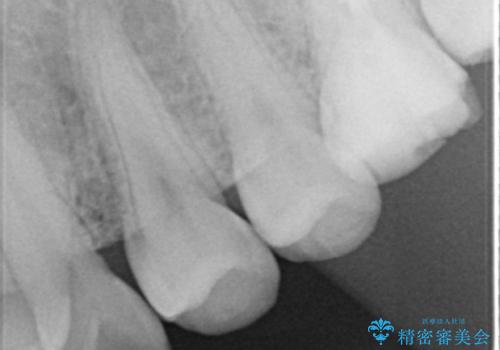

自然な仕上がりにご満足頂けました。

治療終了後、奥歯に残っていた矯正の接着剤を除去し、ホワイトニングも行いました。

クラウンの種類:オールセラミッククラウン スタンダード